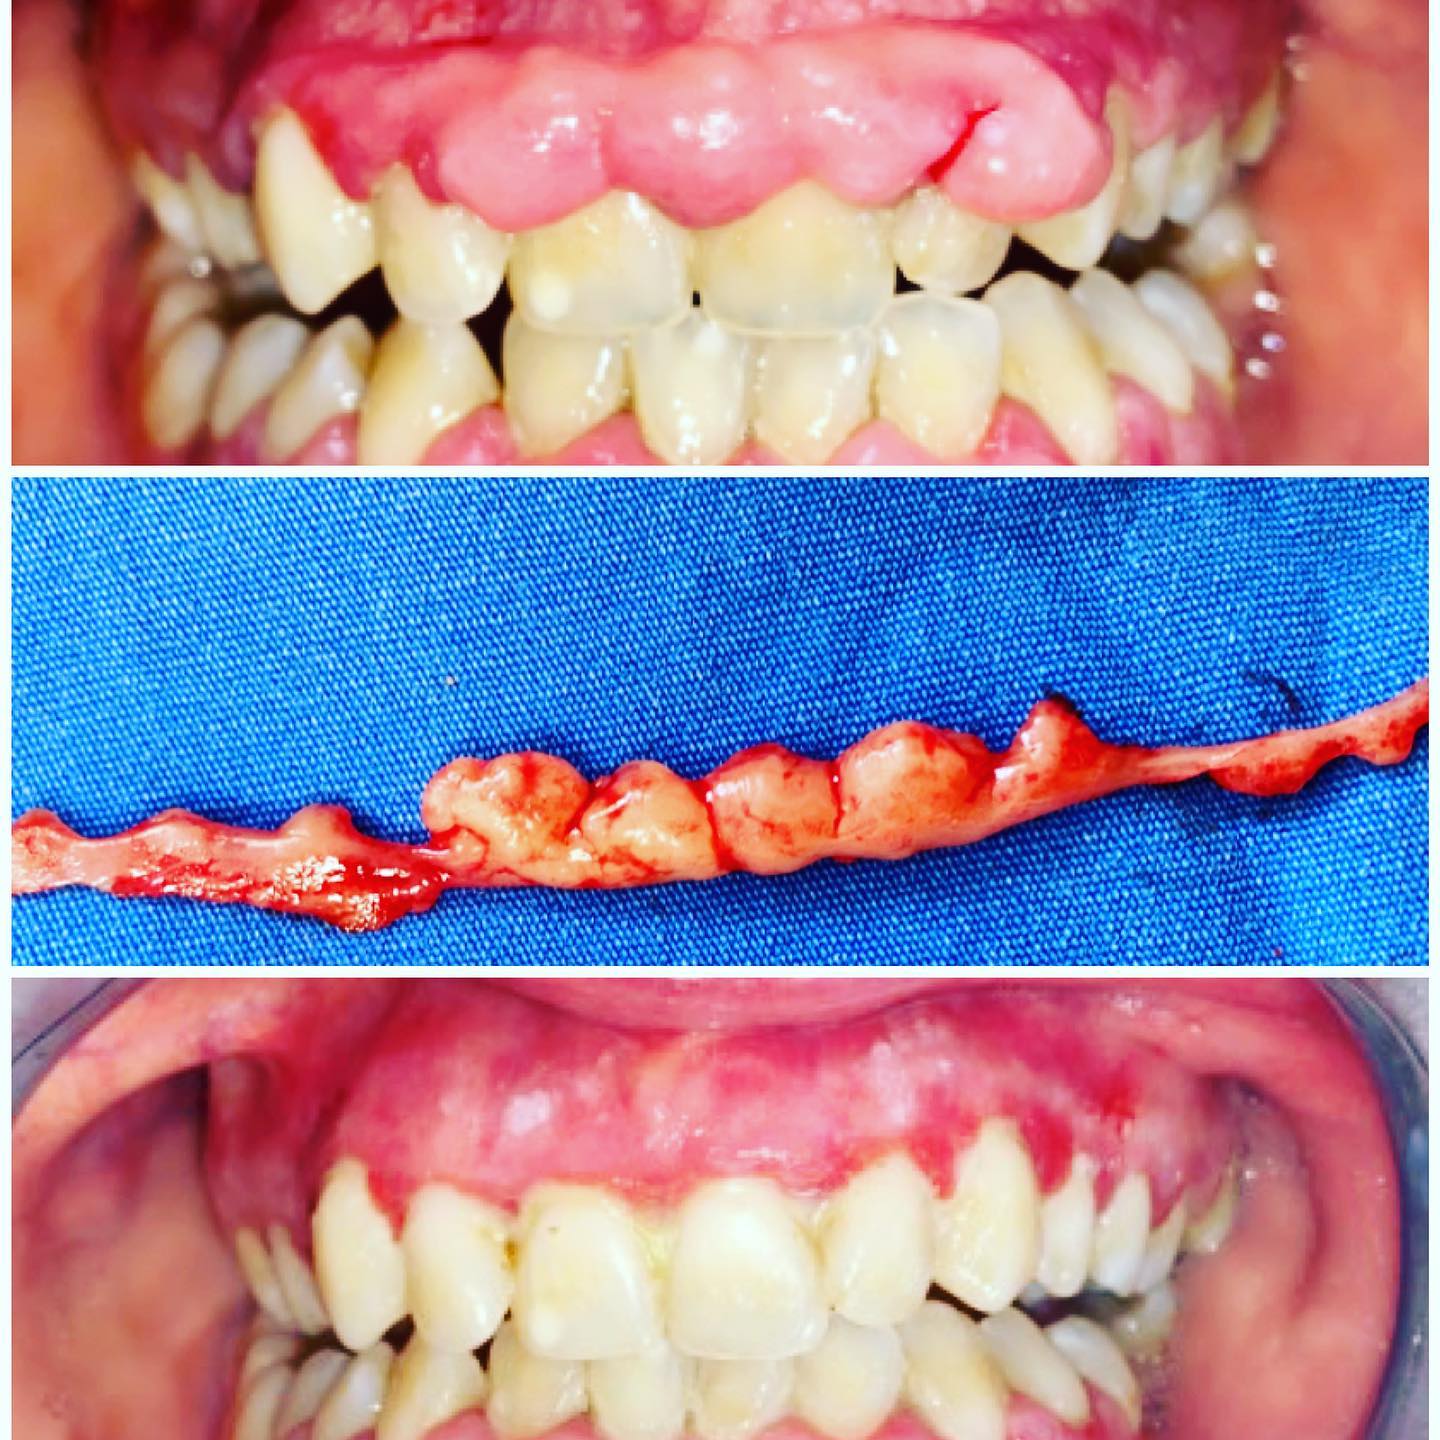

Gingivektomi (gigeniya əksikliyindən və ya bəzi dərmanların istifadəsindən meydana gələn aşırı diş əti böyüməsinin çıxarılması)